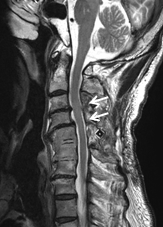

術前MRIでは多椎間で脊髄(灰色)を圧迫しています。後方手術施行後、脊髄への圧迫は改善しています。

頚椎OPLLを認め脊髄を圧迫している状態です。前方からの骨化浮上術により症状は改善しています。

頚椎椎間板ヘルニアを認め脊髄(灰色)を圧迫している状態です。骨移植を伴う頚椎前方固定術により症状は改善しています。